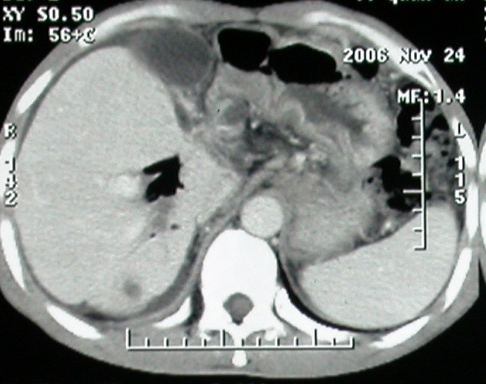

补充一点重要资料:今日查afp大于正常值10倍以上。因此,本病例最大可能应该是肝癌。

手术结果:

肝脏尾状叶肝癌(沿肝十二指肠韧带向下韧带内生长,门腔间隙外压增大),大结节性肝硬化,胆囊积脓,胆道感染。术中见肝外胆道2cm直径,肿瘤向前压迫胆管至扁平状态。